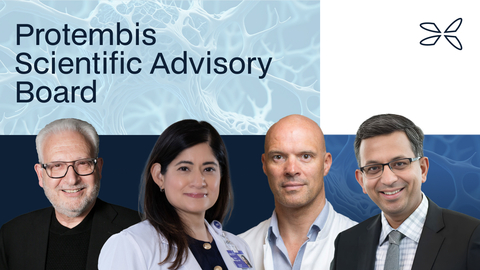

Dr. Martin Leon wordt voorzitter van de nieuwe SAB (Scientific Advisory Board) van Protembis, waarin ook Dr Anita Asgar, Dr Samir Kapadia en Dr Nicolas van Mieghem zullen zetelen

In deze SAB zullen vier internationaal erkende interventionele cardiologen zetelen, die aanzienlijke bijdragen hebben geleverd tot het begrip van de rol bij CEP (Cerebral Embolic Protection = bescherming tegen cerebrale embolie) in TAVR (Transcatheter Aortic Valve Replacement = transkatheter-vervanging van de aortaklep): Dr Martin Leon MD, Dr Anita Asgar MD, Dr Samir Kapadia MD en Dr Nicolas van Mieghem MD.